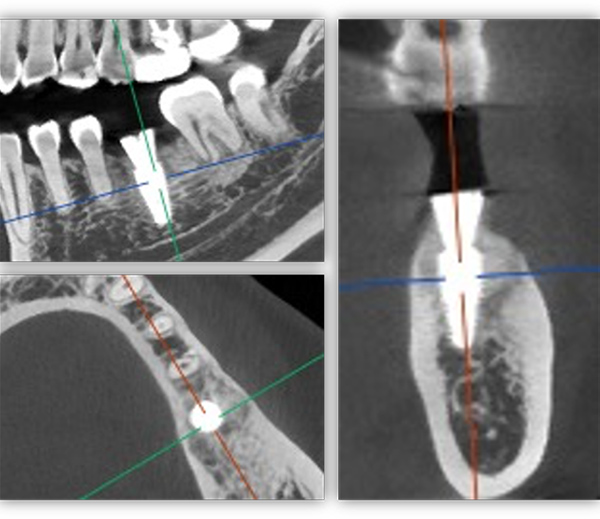

单颗是最常规的种植,不能因为常规就觉得简单,治疗时要追求小而精。从适应证把握到术式选择,再到修复方式,术后的结果有没有达到术前预期效果,都需要用心设计,事后复盘。这位患者是一位来自外地的年轻老师,有一颗6号牙需要种植。她只有在暑假两个月的时间内可以来院,希望能在暑假期间完成治疗。

为满足患者的需求,我为她制订了一个即拔即种、种植后早期负重的方案,把五个治疗步骤缩减为三步。首次来院时,我为她完成了拔牙、种牙和安装基台,6周后来院拆线和取模,两周后完成牙冠修复,也就是戴牙。整个治疗周期仅8周,不到两个月就完成了。

这个病例有一个特点,牙齿还在,但没有功能。从表面看牙冠是完整的,但“金玉其外”,内部已经空了,牙根也烂穿了,无法咀嚼也失去了修复的条件,没有保留价值。

6号牙也就是第一磨牙,是最早萌出的恒牙,比较容易龋坏。它虽然不在前牙美学区,不太容易影响容貌,但出于对美学的高要求,我在设计方案时也考虑了是按常规流程先拔牙,再备洞,还是以修复为导向,先按现有的牙冠来确定未来修复体的形状,再去反推种植体植入的位置。后者对医生来说难度更高一些,但更有利于复原天然牙的形态。

为保证这个方案的顺利实施,我通过查阅文献去印证方案的可行性,还为她建议了适合的种植体,原来三个月的骨结合时间能缩短为两个月,种植体功不可没。